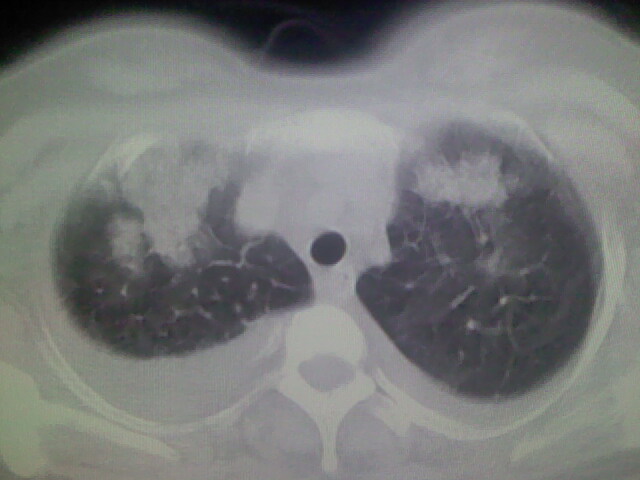

女,24,剖腹产后,突觉胸痛,干咳,不能平卧

双肺“肺泡性肺水肿” “胸腔积液”!

考虑肺梗塞、肺水肿,双侧胸腔积液

临床资料及影象表现支持围产期扩张型心肌病改变,心衰。

考虑产后心肌病,心功能不全,肺水肿,双侧胸腔积液。

考虑产后心肌病,心功能不全,肺水肿,双侧胸腔积液。不排除羊水栓塞可能。